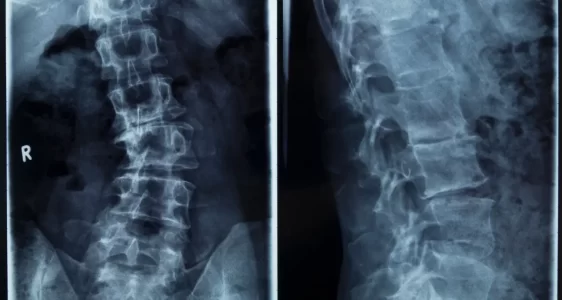

Skolyoz ve kifoz, omurganın normal diziliminden saparak eğrilik oluşturduğu yapısal bozukluklardır. Skolyoz omurganın yana doğru eğrilmesi, kifoz ise öne doğru aşırı kamburluk ile karakterizedir. Bu durumlar yalnızca estetik görünümü etkilemekle kalmaz, aynı zamanda sırt ve bel ağrısı, solunum güçlüğü, hareket kısıtlılığı ve yaşam kalitesinde düşüşe de yol açabilir.

Vidalı düzeltme cerrahisi, omurgadaki eğriliğin titanyum vida ve rod sistemleriyle düzeltilmesini sağlayan modern bir tedavi yöntemidir. Bu ameliyat sayesinde omurga yapısı yeniden dengelenir, deformite giderilir ve hastanın günlük yaşamını daha konforlu sürdürmesi mümkün olur. Mikrocerrahi prensipleri ile gerçekleştirilen operasyonlar, yüksek başarı oranı ve kalıcı sonuçlarıyla öne çıkar.